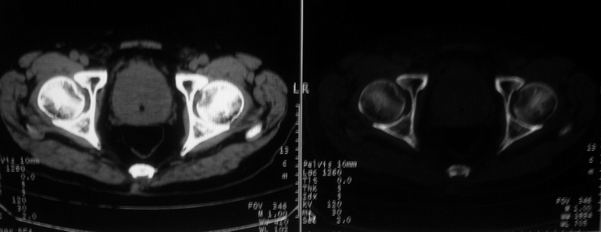

男,85岁,排尿困难。骶椎有问题吗?

前列腺明显增大,突入膀胱,各叶比例协调,密度均匀,精囊腺及精囊角正常;考虑良性增大。

骶骨没有看到明显异常。

1)考虑前列腺增生症并阻塞性膀胱炎。2)骶椎右侧类似囊状骨质密度减低区,边缘骨质硬化,其内为软组织密度影填塞,相邻之骶椎椎管受压变形;考虑为骶椎右侧囊肿或神经纤维瘤。

建议:行mri检查。

1)前列腺明显增大,突入膀胱,各叶比例协调,密度均匀,精囊腺及精囊角正常;考虑前列腺增生症并阻塞性膀胱炎。2)骶椎右侧类似囊状骨质密度减低区,边缘骨质硬化,其内为软组织密度影填塞,相邻之骶椎椎管受压变形;考虑为骶椎右侧囊肿或神经纤维瘤。